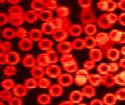

Two-color two-photon absorption has been used to image blood vessels with micrometer resolution, both in vitro and in vivo.

A US team has developed a technique to image hemoglobin in red blood cells with micrometer resolution, but without the need to inject external contrast agents or dyes into the blood. The method might also differentiate between oxy- and deoxyhemoglobin, which would be a crucial step in cancer studies. (Optics Letters, 32, 2641).

The technique employs two-color two-photon absorption, which offers the same performance and resolution as two-photon fluorescence but does not require dyes to be injected into the blood stream. Two collinear synchronized ultrashort laser pulse trains at different wavelengths function as pump and probe, and are coupled into a laser scanning microscope for imaging purposes.

One limiting factor in the team's early images was a reduction in spatial intensity caused by scattering of the probe photons at 650 nm. The signal-to-noise ratio was improved by increasing the probe wavelength to 775 nm and pumping at 650 nm, which enabled observations of complex 3D blood vessel structures.